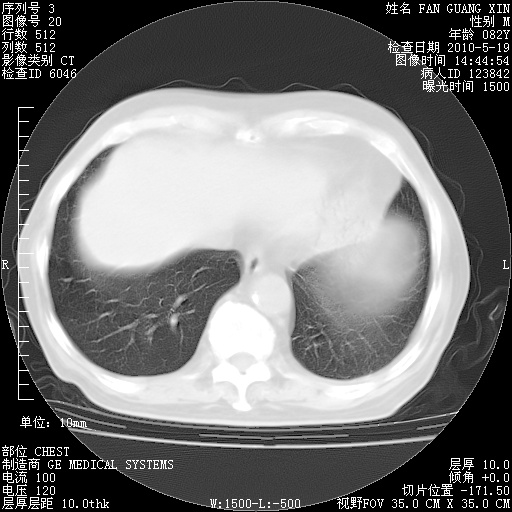

复查肺部CT,明显好转。为什么发热呢?

治疗3周后的肺部CT

治疗3周后的肺部CT纵隔窗